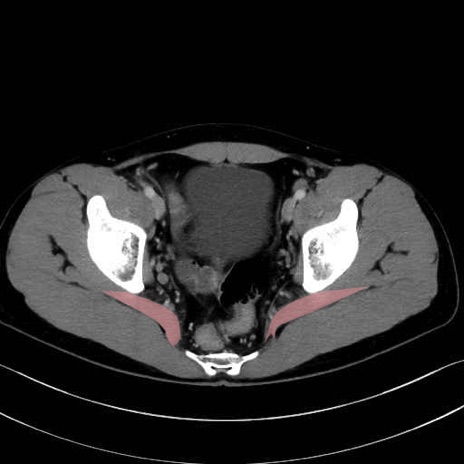

梨状筋 (Piriformis)